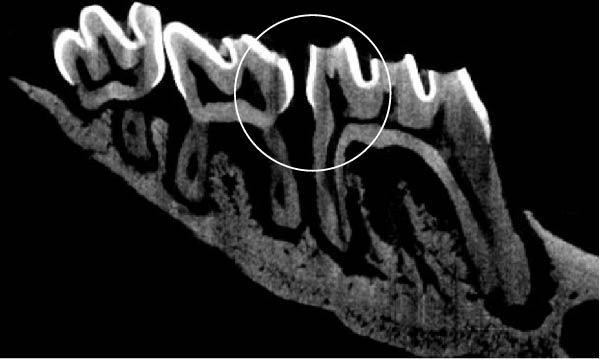

Figure 3 shows the micro‐CT images of OTM in some subgroups.

Figure 3Micro‐CT analysis of OTM after 21 and 40 days: (A) orthodontic treatment/CE injection/stress (chronic); (B) orthodontic treatment/CE injection/stress (acute); (C) orthodontic treatment/stress (chronic); (D) orthodontic treatment/stress (acute); (E) no orthodontic treatment/CE injection/stress (chronic); (F) no orthodontic treatment/CE injection/stress (acute); (G) no orthodontic treatment/no drug (chronic); (H) no orthodontic treatment/no drug (acute).(A)(B)(C)(D)(E)(F)(G)(H)